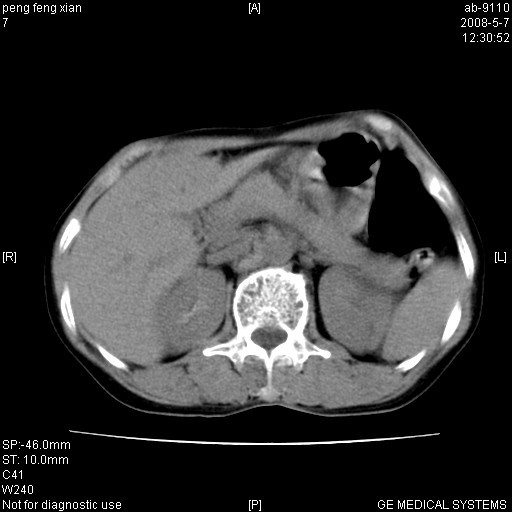

女,56岁。b超左一腹包块,考虑胃肠道肿瘤。

典型胃癌胰体尾部受侵。

胃体部胃壁增厚,不均匀性强化,与胰腺分解欠情.

考虑:胃癌,胰腺受侵待除外.

鉴别:胃淋巴瘤(强化不明显)

建议:胃镜检查.

胃壁增厚,左前胸壁局限性隆起,考虑胃癌可能性大,建议做胃镜

胃底占位待出;右肾结石?